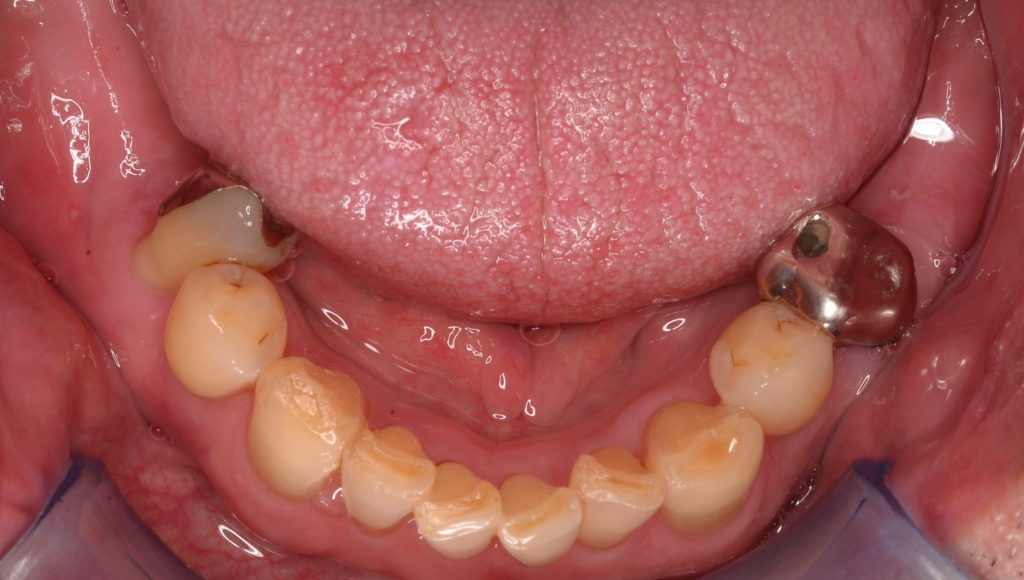

こんにちは✨しんデンタルクリニックです🌸 今回は、歯を失って奥歯で噛めないというお悩みをお持ちだった患者様のご紹介です&…more